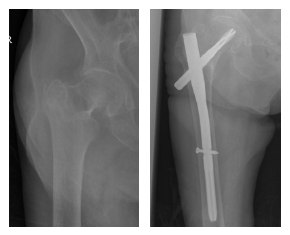

Manis Proximal Femoral Nail System

MANIS Proximal Femoral Nail System is an anti-rotation nail system for the treatment of proximal femoral fracture. The system consists of 4 nails: extra short, short, standard, and long. Instrumentation and completed portfolio provide a good solution for clinical needs.

MANIS Proximal Femoral Nail

Pertrochanteric fractures (31-A1 and 31-A2)

Intertrochanteric fractures (31-A3)

High subtrochanteric fractures (32-A1)